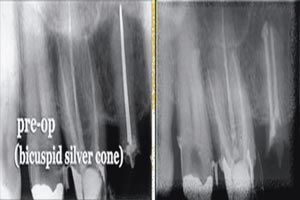

FIGS. 1–2 Radiographs showing an endodontic case that required retreatment (Fig. 1, above). Radiographic evidence colored to highlight the discovery of anomalous pulp stones (Fig. 2, below).

Diagnostics: Foundation of endodontic success

Root canal therapy most likely will be successful if the canal is free of infection when obturated. The optimal approach is an accurate diagnosis to instrumentation strategies thoroughly removing tissue and shaping the coronal midroot and apex. The goals of root-canal therapy involve treating pulpal bacterial infection by removing infected tissues within the chamber, thorough cleansing mirroring the individual root anatomy and effectively sealing the tooth to prevent re-infection (Fig. 1). Careful diagnosis and cleaning of the tooth improves the long-term success rate of endodontic procedures and, at the same time, reduces the chances retreatment will be necessary.